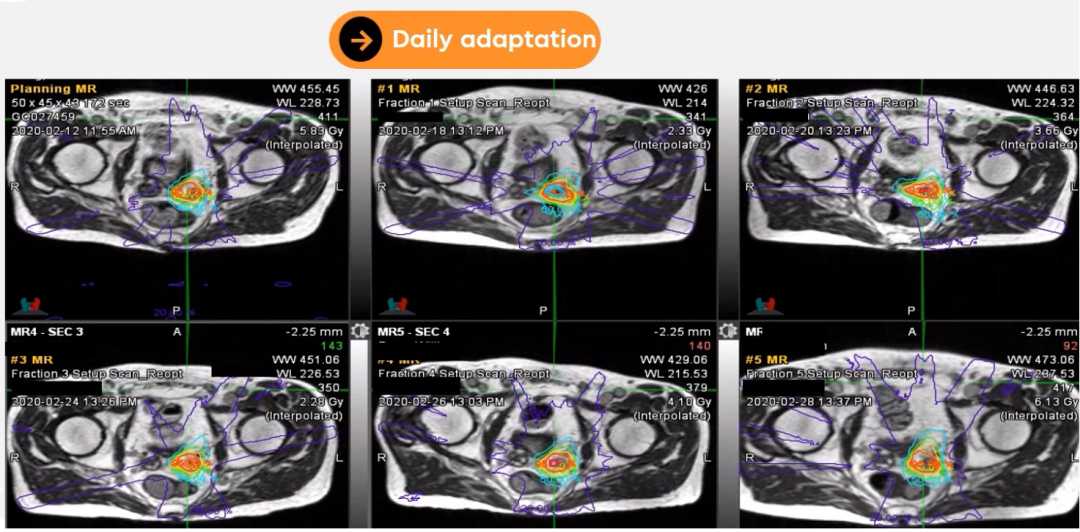

每日自适应:MRIdian允许用户在每日治疗时进行MRI扫描,因此可以看到肿瘤和危及器官(OAR)新的形状和位置,可以据此方便地调整轮廓勾画和在线自适应计划。

通过展示一位左侧精囊腺癌的原始计划和每日自适应计划,清晰显示了靶区和危及器官在每次放疗时均有较大变化,通过MRIdian在线自适应功能,可以在较大程度上修正这些变化,在做到给予靶区高剂量的同时,尽可能的减少危及器官的剂量。

前列腺癌放疗时若使用原计划的剂量分布,会有较大欠量区,可以通过MRIdian在线自适应优化模块方便地改善欠量。

Figure 16前列腺癌放疗时若使用原计划的剂量分布,有较大欠量区(左);在线优化后的剂量分布,无欠量区(右)

Dr. Camilleri表示前列腺放疗的分次间,前列腺的移动度不算大,但精囊腺的移动度较大,可以达到5mm左右,通过MRIdian每日在线自适应计划调整可以修正这些运动。